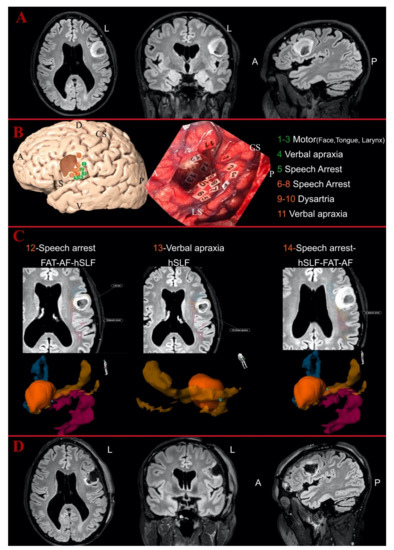

3.3. Intraoperative Findings

3.4. Postoperative Analysis